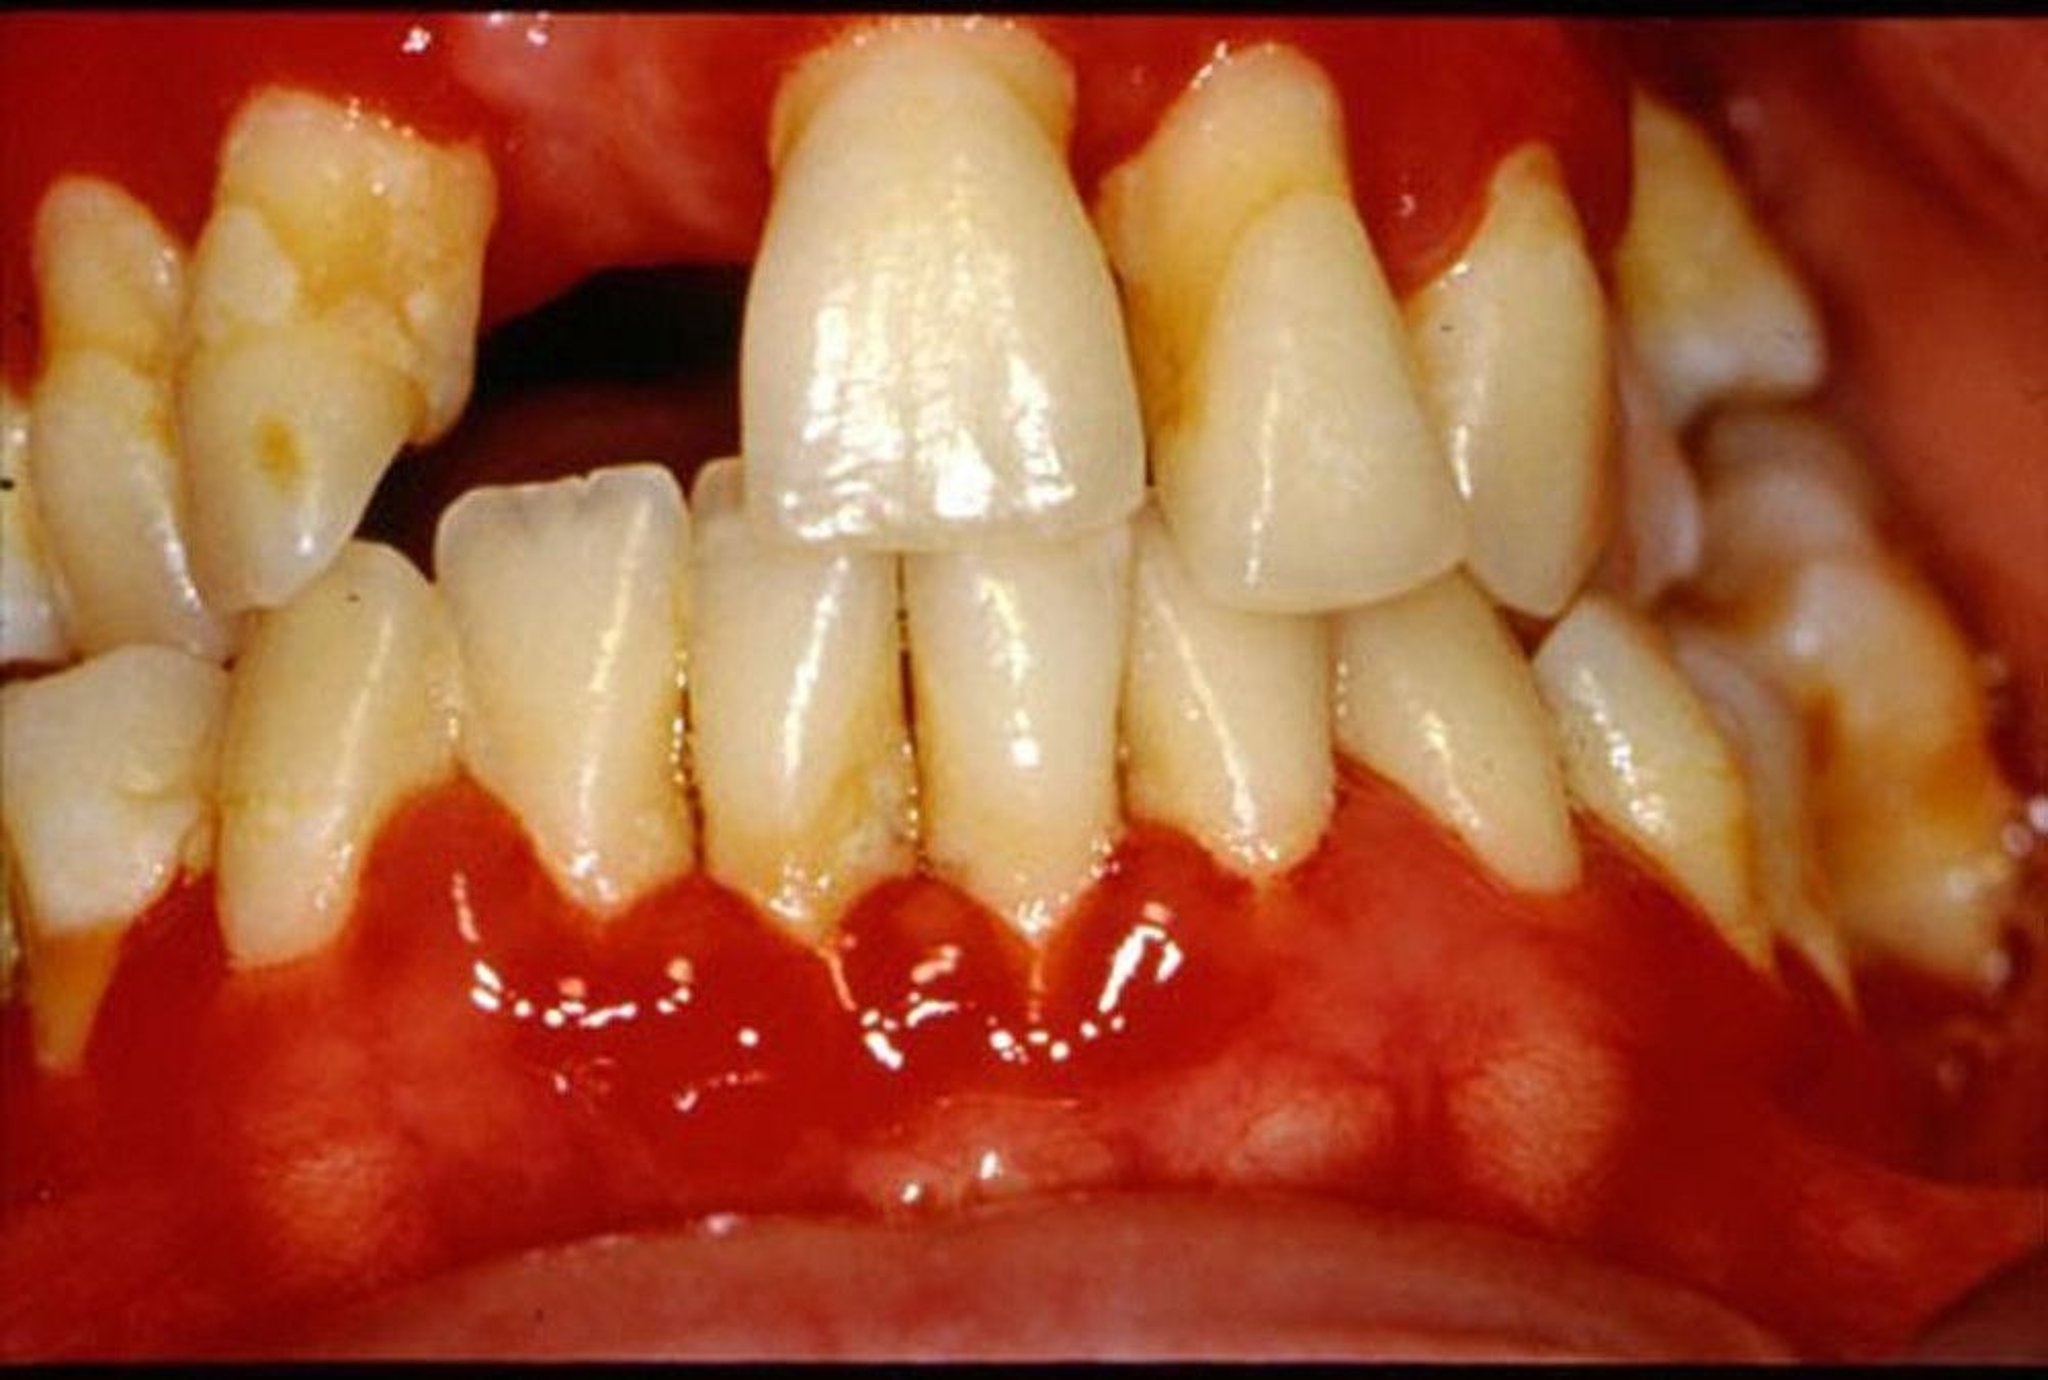

Gusi menjadi merah, bengkak, dan mudah berdarah.

Gingivitis menyebabkan kemerahan dan pembengkakan gusi.

Gambar disediakan oleh Jonathan A. Ship, DMD.

Plak mengiritasi gusi dan membuat kantong di antara gigi dan gusi. Bakteri yang hidup di kantong ini dapat menyebabkan gingivitis serta gigi berlubang di akar gigi. Gusi tampak merah dan bengkak serta menjadi bisa digerakkan alih-alih keras dan kencang menahan gigi. Gusi dapat berdarah dengan mudah, terutama saat menyikat gigi atau makan. Orang biasanya tidak mengalami nyeri.